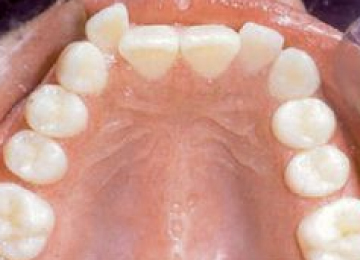

Сапфировые брекеты: фото До и После

Брекеты из сапфиров для исправления прикуса крепятся только на переднюю часть зубов. Различают лигатурные и безлигатурные брекет-системы.

Сапфировые конструкции имеют одну особенность – они в несколько раз дороже. Поэтому чаще всего врач предлагает провести ортодонтическое лечение комбинированными моделями, где установлены прозрачные сапфировые брекеты только на передних зубах, а на жевательных, невидимых извне – металлические.

Прозрачные брекеты и замочки уменьшенных размеров, а также покрытие дуги в светлые оттенки, делают их невидимыми и не привлекают внимание. Пациенты могут не стесняться, даже если их эмаль не совсем белая. На протяжении всего времени, от начала лечения до конца, они остаются в первоначальном виде.